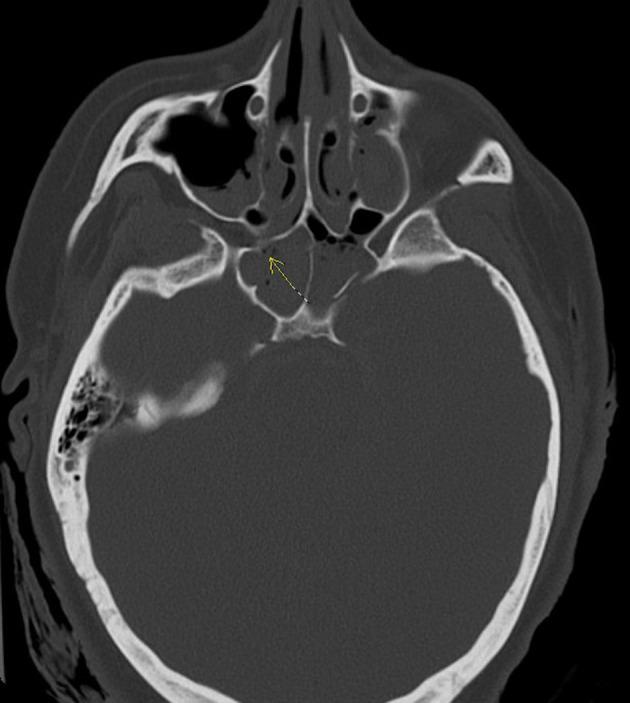

A 24-year-old female with history of traumatic brain injury with associated skull fractures due to a gunshot wound to the head 6 months prior presented to the ED in hemorrhagic shock secondary to epistaxis. After stabilization with the administration of blood products, Computed Tomography with Angiography (CTA) imaging of the head and neck was obtained and revealed a 3.1 × 2.2 × 2.5 cm pseudoaneurysm of the cavernous portion of the right internal carotid artery penetrating through the base of the skull into the ethmoidal sinus. The patient was taken for formal angiography by interventional radiology-and a partially thrombosed daughter sac of the initial aneurysm was identified and believed to be the source of the hemorrhage. The aneurysm was successfully coiled and occluded using ONYX embolization. Postoperatively, the patient returned to her baseline mental status without any acute complaints. The patient was discharged back to her nursing home 2 days later with a 3-week follow-up CTA revealing persistent occlusion of the aneurysm and a patent internal carotid artery.

一名24岁女性,6个月前因头部枪伤导致创伤性脑损伤并伴有颅骨骨折,因鼻出血继发失血性休克被送往急诊科。在输注血液制品使其病情稳定后,对头颈部进行了计算机断层血管造影(CTA)成像检查,结果显示右侧颈内动脉海绵窦段有一个3.1×2.2×2.5厘米的假性动脉瘤,该动脉瘤穿过颅底进入筛窦。患者被介入放射科送去进行正式血管造影,发现了最初动脉瘤的一个部分血栓形成的子囊,并认为这是出血源。使用Onyx栓塞剂成功地对动脉瘤进行了弹簧圈栓塞和封堵。术后,患者恢复到基线精神状态,无任何急性不适主诉。患者于两天后出院回到养老院,3周后的CTA随访显示动脉瘤持续闭塞,颈内动脉通畅。